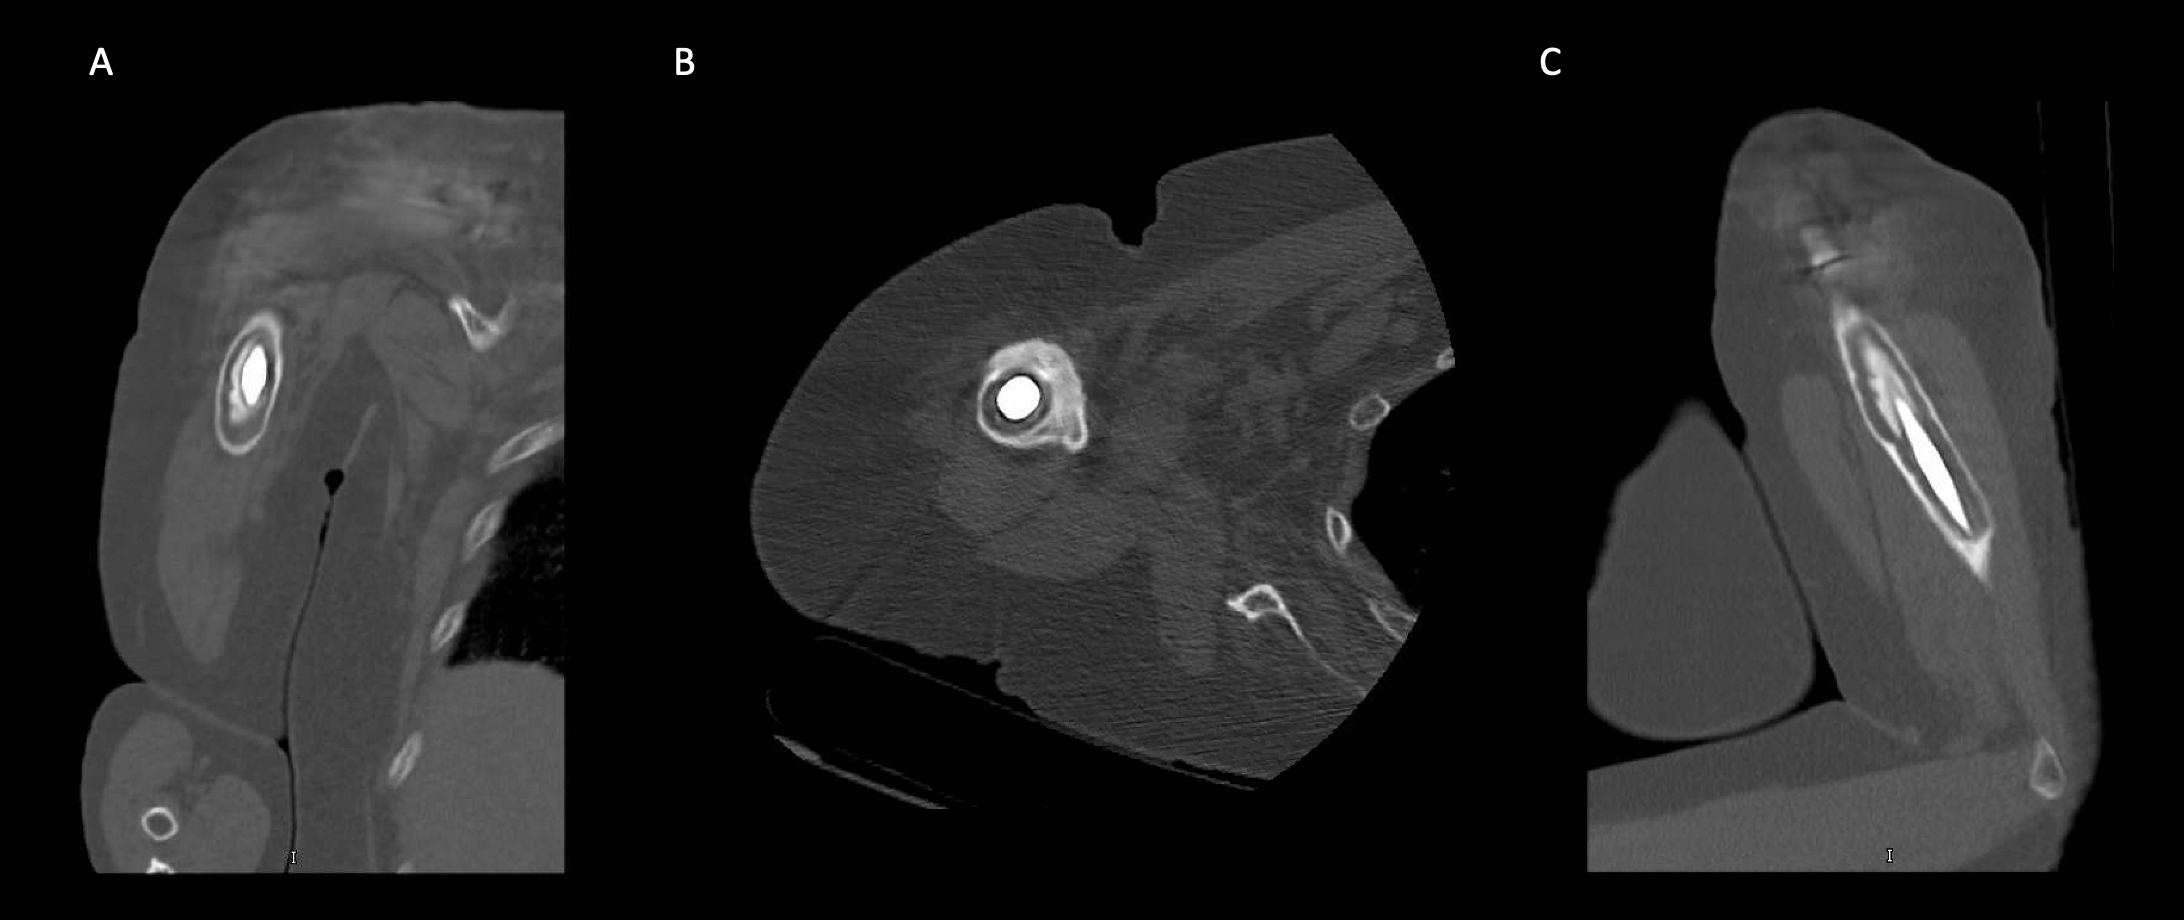

A 69-year-old woman presented after resection arthroplasty of her right shoulder hemiarthroplasty and completion of antibiotic treatment for culture negative PJI for evaluation of reconstructive options. She had a history of a displaced two-part right proximal humeral fracture which was repaired with an intramedullary nail. Post operatively, she had persistent pain and CT scan of the shoulder showed two screws in the humeral head that extended through the cortex and into the glenohumeral joint. The screws were removed and replaced with smaller screws. Subsequently, she had non-union of the fracture in the setting of deltoid weakness and was revised to a right hemiarthroplasty (Figures 1-3). Post operatively, she had persistent pain refractory to physical therapy and diminished function that was impacting her quality of life. She sought subsequent care, and there was concern for arthroplasty failure secondary to a septic versus aseptic condition and the decision to proceed with resection arthroplasty was made. During resection arthroplasty, a significant amount of fluid was expressed from the joint space. The combination of the clinical picture of progressive and persistent pain and the gross expression of fluid were concerning for PJI and the decision to treat was made. It was felt that the extent of humeral bone loss did not allow for a stable cement spacer, so none was placed. Intraoperative joint fluid cultures, anaerobic, and fungal cultures were all negative for growth. Cultures were held for 21 days to rule out C. Acnes infection. Considering the plan for future reimplantation, infectious disease consultation recommended a 6-week course of vancomycin but after 2 days the patient had a transfusion reaction and was switched to daptomycin. She was left with markedly limited active motion associated with severe pain. After completion of the antibiotic course, the patient elected to proceed with revision surgery. This patient had a flattened and distorted glenoid and atrophied rotator cuff musculature demonstrated prior to resection arthroplasty on CT (Figure 4). This patient’s prior hemiarthroplasty had been a tantalum coated, cemented humeral stem with associated marked thinning of the humeral cortex even prior to resection arthroplasty, and this resulted in a large amount of proximal humeral bone loss during the resection (Figure 5). The patient was severely debilitated by the right shoulder and wanted to proceed with reconstruction. Because of the combination of glenoid and humeral bone loss and the lack of rotator cuff attachments, a custom constrained prosthesis design process was initiated, and the implant was available 16 months after the resection arthroplasty. Preoperative 3 phase SPECT (Single Photon Emission Computed Tomography) three phase bone scan, upper extremity CT, and blood work (WBC 5.4, ESR 9, CRP 0.8) showed no suggestion of active infection.

A 62-year-old woman presented for evaluation of her reconstructive options after resection arthroplasty of a right rTSA and completion of antibiotic treatment for culture negative PJI. Her rTSA had been an Encore prosthesis placed due to rotator cuff arthropathy (Figures 6). Post-operatively she had persistent pain, stiffness, and tenderness to palpation that was treated with physical therapy, a steroid injection, and manipulation under anesthesia. An infectious work up due to the chronic and persistent nature of the pain showed WBC 7.4, ESR 53, CRP 1.2. Patient denied further work up with a tagged white cell scan and preferred continued clinical monitoring to observe pattern of symptoms. Eleven months later, she endorsed persistent pain. Repeat infectious work up showed WBC 4.5, ESR 13, and CRP 1.1. Despite the normal inflammatory markers, a 10-day trial of Augmentin was initiated and failed to change her symptoms. The decision to proceed with 1 vs 2 stage reconstruction was made. During resection arthroplasty, a substantial amount of fluid was expressed from the joint capsule concerning for PJI. A cement spacer was placed, and the patient was treated with 6 weeks of vancomycin and cefepime (Figure 7). There was proximal humeral bone loss as the result of resection arthroplasty due to the humeral stem. The glenoid component was loose and associated with glenoid bone loss, further complicated by the need for removal of a broken central screw (Figure 8).

Case 2. At the latest follow-up one-year post-op, the patient expressed that the pre-operative pain had resolved after the operation. Despite this, she stated that if given the option again she would not undergo the surgery because she did not attain the function she expected and felt that her function may have decreased compared to pre-op. Overall stability and alignment were good. On physical exam, she was able to reach within 1 inch from her mouth and had 20 degrees abduction and 5 degrees forward flexion actively. Active elbow flexion was 0 to 120 degrees (Figures 14). At 2 years post-op she had some regression in her pain but accompanied by modestly decreased AROM. Shoulder AROM was 15 degrees abduction, and 5 degrees forward flexion. Elbow AROM was from 0 to 105 degrees of elbow flexion. CT scan showed increased lucency surrounding the humeral component concerning for osteolysis and prosthesis loosening (Figure 14). Blood work at the 2-year mark to investigate the radiolucencies and decreased AROM left us with low suspicion for infection (WBC 5.4, ESR 33, CRP <3.0).